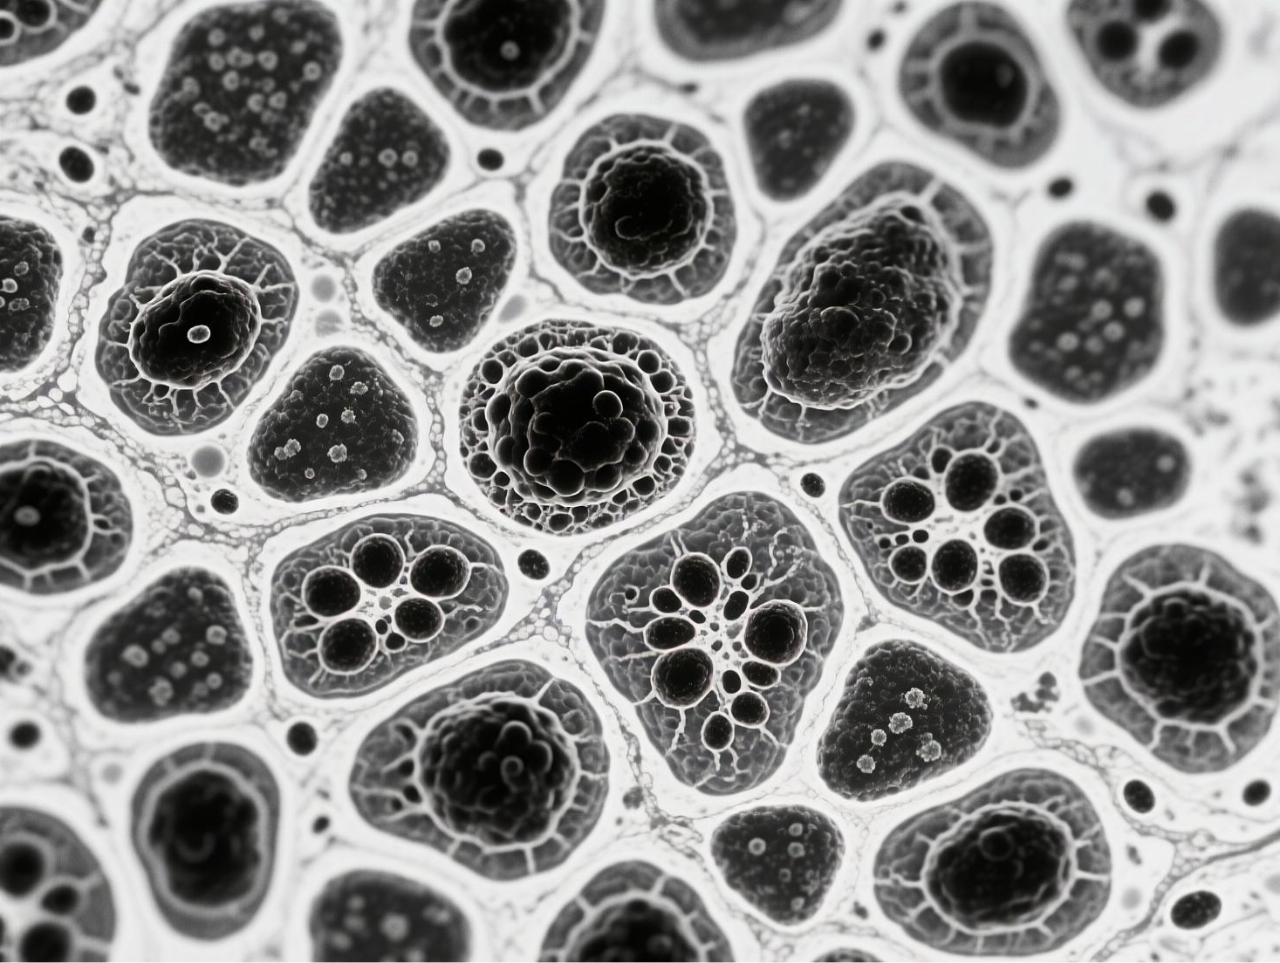

图 BCG-MBs的制备与表征

台式扫描电镜在本研究中发挥了关键的表征作用,为微气泡系统的结构验证提供了直观而精确的证据。研究团队使用188博金宝网页官网ZEM18台式扫描电镜对冻干后的BCG-MBs进行金溅射镀膜处理后,在不同放大倍数下观察其表面形态,清晰地展示了微气泡规则的球形结构以及BCG在微气泡表面的不规则分布状态。这一表征不仅确认了微气泡制备工艺的成功,还直观揭示了BCG在微气泡中的物理分布特征,为理解药物释放机制提供了结构基础。扫描电镜图像作为重要的形态学证据,有力支持了后续对微气泡浮力特性、药物释放行为及生物效应的分析,是连接材料设计与功能验证的关键环节。